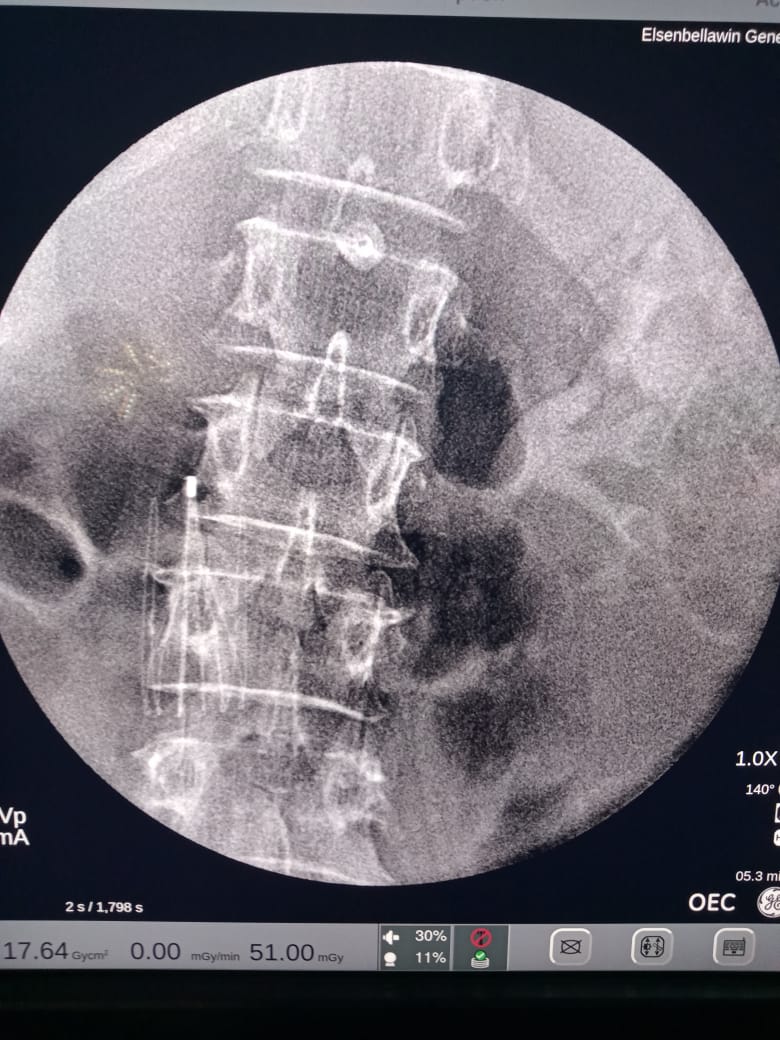

أعلن الدكتور سعد مكي وكيل وزارة الصحة بالدقهلية عن نجاح فريق طبي بإجراء عملية تركيب فلتر بالوريد الأجوف السفلي لمريضة تبلغ من العمر 52 عاما كانت تعاني من نزيف حاد بالمخ وجلطة حادة بالوريد الفخذي الأيمن ونظرا لعدم إمكانية علاج الحالة بأدوية السيولة التي ستزيد من النزيف مما يسبب خطرا بتشكل جلطة رئوية ويهدد حياتها.

وعلي الفور قرر الفريق الطبي تركيب فلتر في الوريد الأجوف السفلي لمنع انتقال التجلطات من الساقين او الحوض الى الرئتين او القلب وهذه العملية تعد هي الاولى من نوعها التي يتم اجراؤها بمستشفى السنبلاوين العام

اجريت الجراحة تحت اشراف الدكتور حسام رشدي استاذ جراحة الأوعية الدموية بجامعة المنصورة ورئيس وحدة جراحة الأوعية الدموية بمستشفى السنبلاوين، الدكتور محمد عبد العزيز اخصائي جراحة الأوعية الدمويه بالمستشفى، الدكتور خالد البلتاجي أخصائي جراحة الأوعية الدموية.